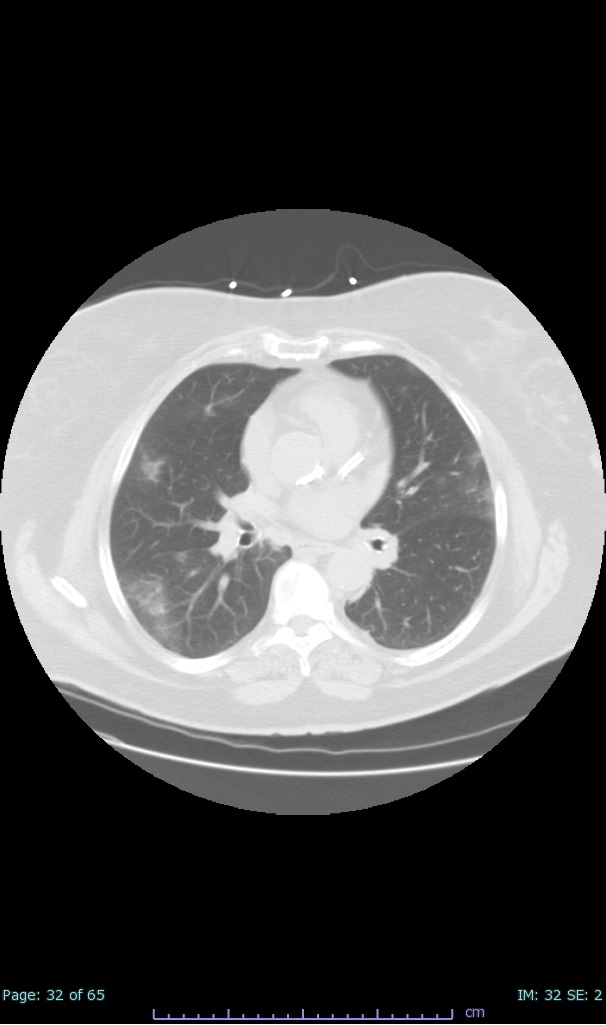

- 100% subpleural involvement, 33% + centrolobular involvement

- 40% even apical/basilar, 27% basilar dom, 5% mid dom. 1/17

- 66% had some + CXR finding I could correlate to a CT finding